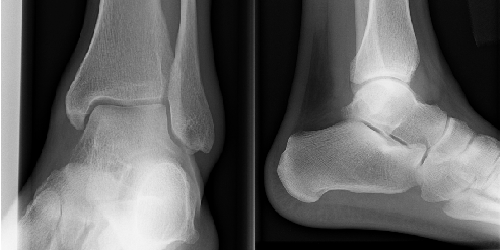

Mortise view of right ankle

AP view of left ankle

There are no fractures in any of the above images. This is a very common finding for a patient presenting with ankle swelling and tenderness. While no fractures were present, one can see the closing epiphyses of the distal tibia and fibula in each image. They are apparent as sclerotic bands in the distal region of each bone. Did you see them?